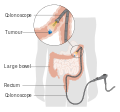

Bowel cancer may be diagnosed by obtaining a sample of the colon during a sigmoidoscopy or colonoscopy.[3] This is then followed by medical imaging to determine if the disease has spread.[1] Screening is effective for preventing and decreasing deaths from colorectal cancer.[6] Screening is recommended starting from the age of 50 to 75.[6] During colonoscopy, small polyps may be removed if found. If a large polyp or tumor is found, a biopsy may be performed to check if it is cancerous. Aspirin and other non-steroidal anti-inflammatory drugs decrease the risk.[4][7] Their general use is not recommended for this purpose, however, due to side effects.[8]

Colorectal cancer diagnosis is performed by sampling of areas of the colon suspicious for possible tumor development, typically during colonoscopy or sigmoidoscopy, depending on the location of the lesion. Disease extent is usually determined by a CT scan of the chest, abdomen and pelvis. Other potential imaging tests such as PET and MRI may be used in certain cases. Colon cancer staging is done next, based on the TNM system which considers how much the initial tumor has spread, if and where lymph nodes are involved and the extent of metastatis.[15]

As more than 80% of colorectal cancers arise from adenomatous polyps, screening for this cancer is effective not only for early detection but also for prevention.[75] Diagnosis of cases of colorectal cancer through screening tends to occur 2–3 years before diagnosis of cases with symptoms.[15] Any polyps that are detected can be removed, usually by colonoscopy or sigmoidoscopy, and thus prevented from turning cancerous. Screening has the potential to reduce colorectal cancer deaths by 60%.[76]

The four main screening tests are fecal occult blood testing, flexible sigmoidoscopy, colonoscopy, and stool DNA screening test.[15] Of the three, only sigmoidoscopy cannot screen the right side of the colon where 42% of malignancies are found.[77] Virtual colonoscopy via a CT scan appears as good as standard colonoscopy for detecting cancers and large adenomas but is expensive, associated with radiation exposure, and cannot remove any detected abnormal growths like standard colonoscopy can.[15]

If the cancer is found at a very early stage, it may be removed during a colonoscopy.[1] For people with localized cancer, the preferred treatment is complete surgical removal with adequate margins, with the attempt of achieving a cure. This can either be done by an open laparotomy or sometimes laparoscopically.[15] The colon may then be reconnected or a person may have a colostomy.[1]